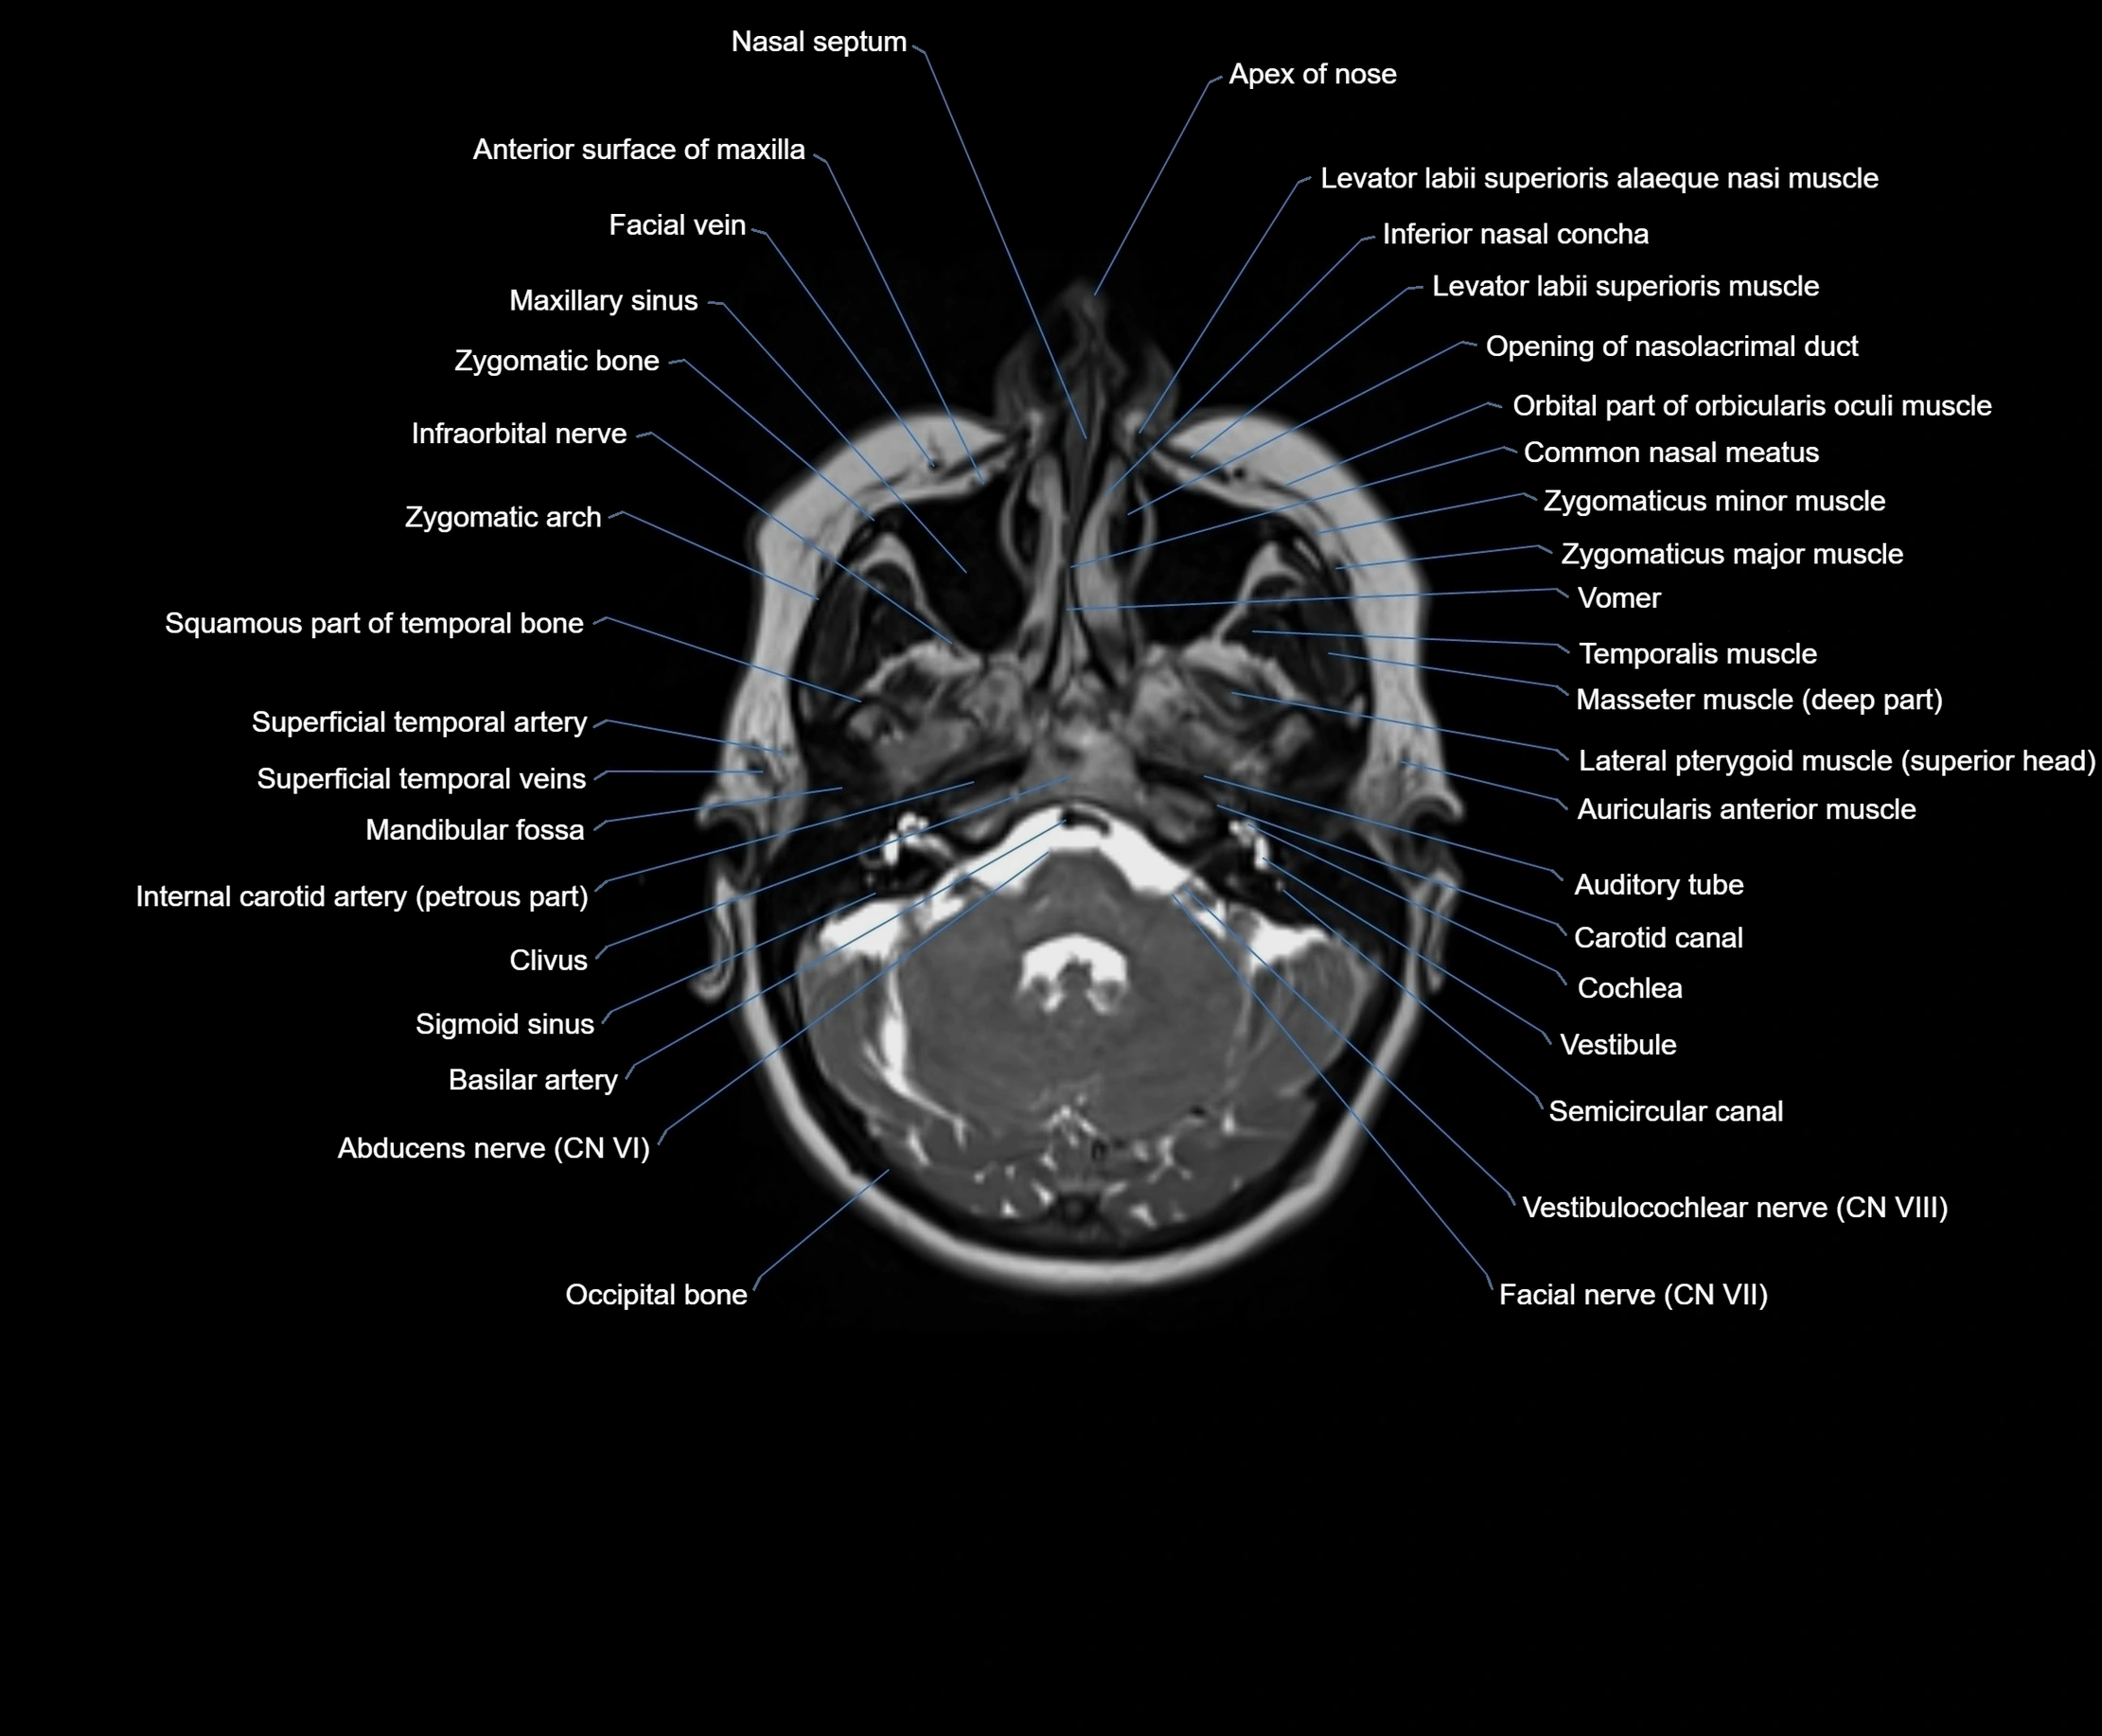

MRI images